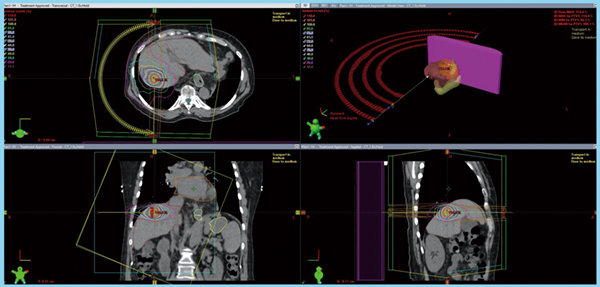

当院では乳がんの術後照射はすべてCLINAC 21EXで行い,肺と肝臓の体幹部定位放射線治療(SBRT)はCLINAC 21EXとHalcyonの両方で治療計画を立て,線量分布を比較した上で良い方を選択している。結果として,肝SBRT(図2)や直腸がんの術前照射,前立腺がんの照射は,全例Halcyonで行っている。肝SBRTの呼吸性移動対策には,光学式患者ポジショニングシステム「AlignRT Inbore」(VisionRT社製)を用い,全例息止め照射を行った。このほか,電子線照射が必要となるケロイド全例と,緊急・準緊急の対応が求められる転移性骨腫瘍の緩和照射の多くは,CLINAC 21EXで行っている。

図2 HCCに対するSBRTの治療計画の一例